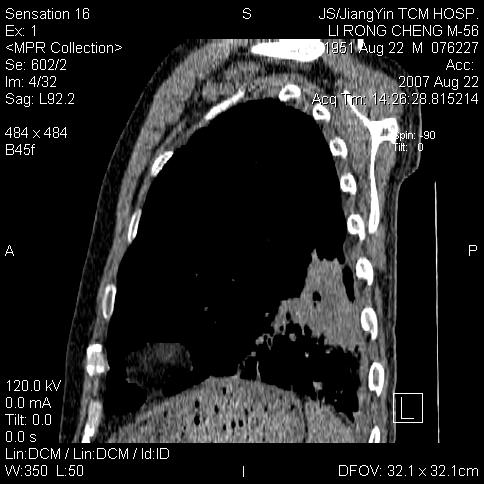

边灶边缘较光整,冠状位病灶呈大片状,,内有空洞,有胸膜反应,但无明显胸膜外侵犯征像,结合病史支持考虑肺肿脓,不排除结核,治疗后复查

好多钙化灶哦,病灶位于下叶背段,或许考虑结核更合适,做下相应检查先

左肺下叶支气管呈小囊状扩张。下叶背段有类圆形高密度影,边缘模糊,外与胸膜相连。左侧胸膜增厚粘连。心包膜增厚。结合病史考虑1支扩并感染2胸膜及心包炎。

左下肺团片状类软组织密度影,形态不规则,边缘欠规整,其内可见液化区及气体影,病灶内侧见引流支气管影,相邻胸膜反应性增厚。病灶周围肺野内见增粗支气管,壁厚,边缘模糊。考虑:支气管扩张并感染;肺脓肿。